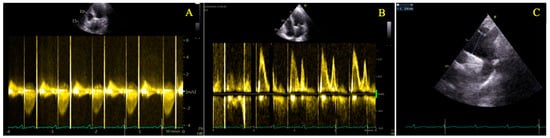

| Gestational Age (Weeks) | Heart Rate (bpm) | Hb (g/dL) | NT-proBNP (pg/mL) | 6mWT (m) | LVEF (%) | LVOT VTI (cm) | AV VTI (cm) | Maximum AV Gradient (mmHg) | Mean AV Gradient (mmHg) | Indexed Aortic Valve Area (cm2/m2) |

|---|---|---|---|---|---|---|---|---|---|---|

| 22 | 76 | 11.5 | 45 | 670 | 59 | 27.5 | 99.3 | 96 | 58 | 0.475 |

| 26 | 73 | 60 | 27.3 | 99.2 | 94 | 60 | 0.475 | |||

| 29 | 82 | 11.4 | 59 | 625 | 60 | 26.9 | 99.8 | 93 | 60 | 0.463 |

| 30 | 85 | 61 | 27 | 102 | 108 | 60 | 0.457 | |||

| 31 | 81 | 60 | 26.9 | 101.8 | 95 | 58 | 0.469 | |||

| 32 | 78 | 12.1 | 67 | 630 | 59 | 27.2 | 100 | 103 | 62 | 0.469 |

| 33 | 76 | 59 | 27.5 | 99.5 | 100 | 61 | 0.475 | |||

| 34 | 84 | 61 | 27.9 | 101 | 101 | 60 | 0.475 | |||

| 35 | 82 | 12.5 | 37 | 615 | 61 | 28 | 100.6 | 95 | 55 | 0.481 |

| 36 | 80 | 60 | 26.4 | 99 | 89 | 52 | 0.463 | |||

| 37 | 85 | 12.6 | 62 | 27 | 100 | 93 | 56 | 0.469 | ||

| 38 | 86 | 12.3 | 66 | 575 | 62 | 26.5 | 99.8 | 92 | 55 | 0.457 |

| 3 months postpartum | 70 | 11.9 | 54 | 654 | 60 | 28.3 | 118 | 103 | 68 | 0.50 |